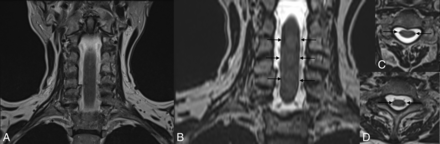

Furthermore, we think it would be useful for the reader if some of the limitations of 3D T2-SPACE were mentioned, such as the visualization of false superficial siderosis, which can randomly appear in the sagittal, coronal, or axial planes, as illustrated in Fig 1.

T2 TSE (A) and 3D T2-SPACE (B) in the coronal plane. Note linear low signal intensity on both sides of the spinal cord (arrows, B) on 3D T2-SPACE, also visible on the axial plane (C and D), mimicking superficial siderosis.